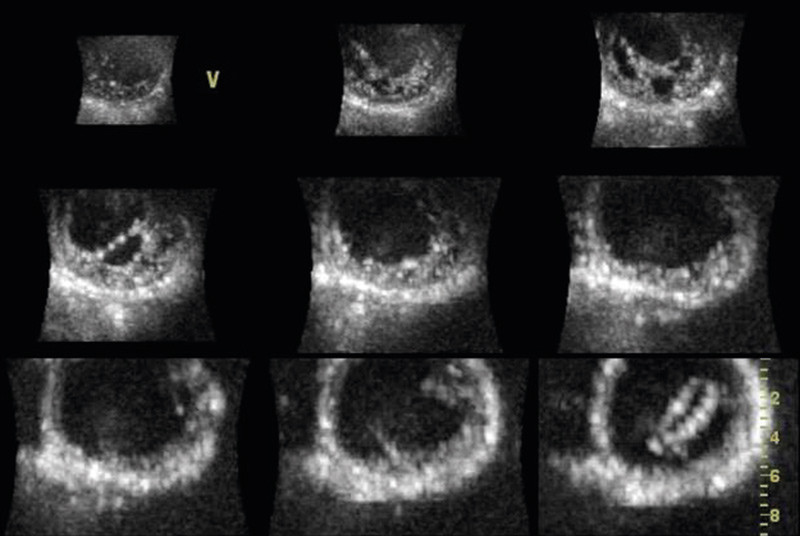

Ved hjelp av 3D-ekko med fullvolumopptak kan venstre hjertekammer fremstilles som multiple kortakser på skjermen (fig 4). Ved hjertemuskelsykdommer som hypertrofisk kardiomyopati får man bedre oversikt over fordelingen av hypertrofien. Spesielt ved mer apikale varianter kan dette være nyttig, da disse kan bli oversett ved rutineekkografi. Enkelte sjeldnere former for kardiomyopatier, som manglende modning av myokard (non-compaction cardiomyopathy), har karakteristiske trekk som lett kan fremstilles med 3D-ekko (fig 5). Det foreligger imidlertid foreløpig ingen god dokumentasjon på tilleggsnytten av tredimensjonal ekkografi ved ulike kardiomyopatier.